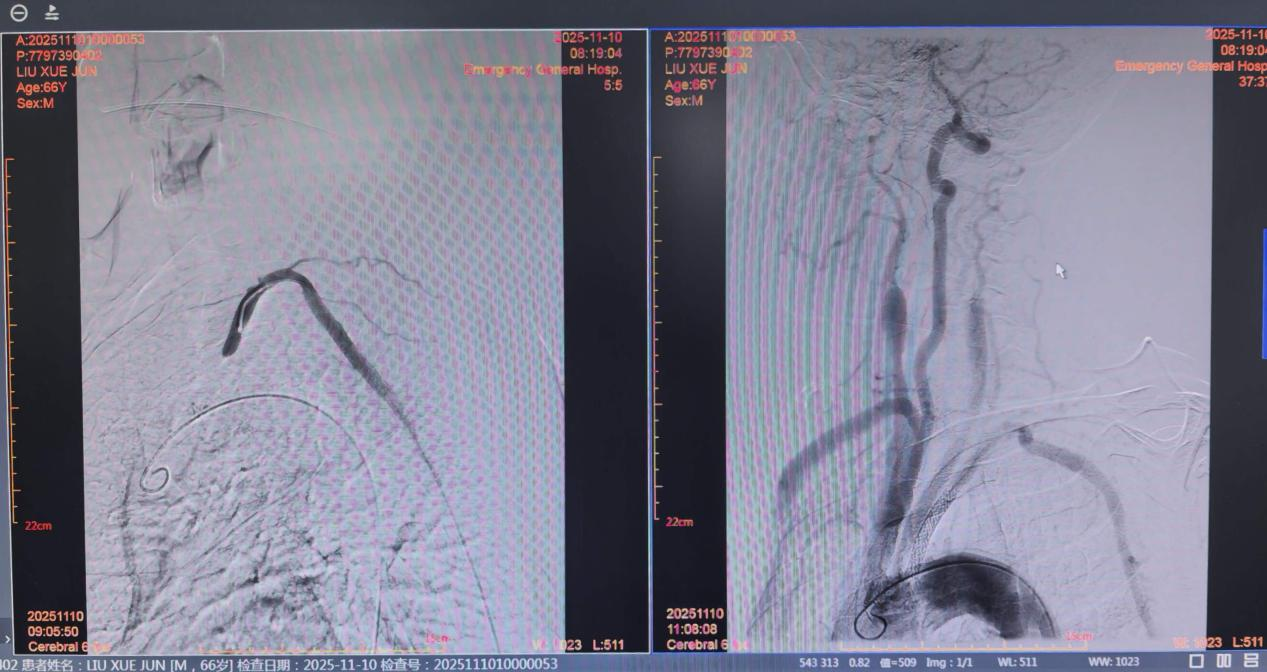

4. 有创检查:数字减影血管造影(DSA) 是诊断的“金标准”,能动态观察血流方向,但鉴于其有创性,通常在准备进行介入治疗时使用。

· 介入治疗(微创):这是目前的主流方法。经皮穿刺动脉血管,置入球囊扩张狭窄或者闭塞部位,并植入支架撑开病变血管。该方法创伤小、恢复快。